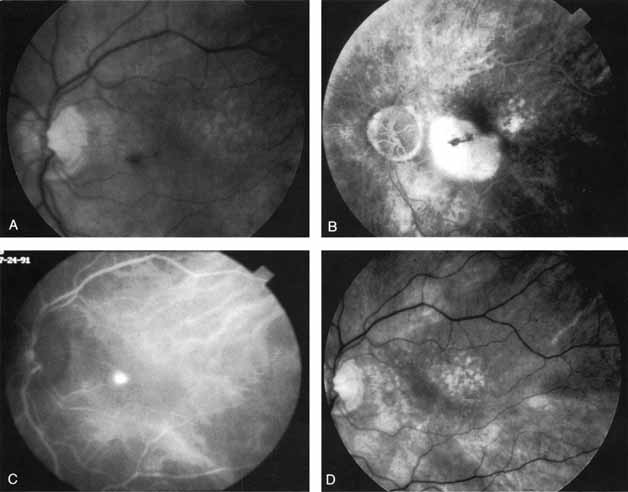

In a landmark article, Yannuzzi and associates18 demonstrated that ICG videoangiography was extremely useful in identifying well-demarcated localized areas of neovascularization in what had been classified as occult CNV by standard fluorescein angiography.19–24 In this study, 39% of 129 patients with “occult CNV” originally diagnosed as determined by fluorescein angiography were given a revised diagnosis of “well-defined neovascular lesions” based on the information obtained from the ICG study (Fig. 1). One study revealed that approximately 40% of patients with occult CNV diagnosed actually presented with early, well-defined focal areas of fluorescence on ICG videoangiography.25 They further defined two potential subgroups of occult CNV: those with and those without serous pigment epithelial detachments (PEDs) accompanying the occult neovascular process. They also pointed out that ICG angiography offered a potential advantage in identifying neovascular lesions when there was clinical evidence of recurrent CNV after previous laser photocoagulation treatment.

Subsequently, Yannuzzi and colleagues25 and Guyer and associates26 evaluated the usefulness of ICG angiography in identifying localized areas of CNV in patients with occult CNV with or without a serous PED. In a careful evaluation of more than 680 patients, they identified 22% of patients with localized lesions that might be amenable to laser therapy—lesions that would otherwise be classified as untreatable based on guidelines for laser photocoagulation (Figs. 2 and 3). As a result of this improved imaging technique, as many as two to three times the number of patients would have been potentially eligible for laser treatment than would have been treatable based on fluorescein angiography alone.

An important report by Chang and co-workers27 lends support to the rationale for interpreting the hyperfluorescence seen on ICG angiography as CNV. In this clinicopathologic study, a patient was identified who had experienced subretinal hemorrhage with early signs of occult CNV on fluorescein angiography (Fig. 4A). Fluorescein angiography demonstrated blocked fluorescence (Fig. 4B). The ICG study, however, demonstrated late staining in a well-circumscribed fashion, which the authors interpreted as a “plaque” of occult CNV (Fig. 4C). When the patient died, this area was evaluated and studied histopathologically and compared with the picture seen on ICG angiography. The area of hyperfluorescence on the ICG study corresponded precisely to a thin layer of fibrovascular tissue beneath the pigment epithelium and neurosensory retina, confirming that the late-staining tissue imaged with ICG angiography was truly a neovascular membrane (Fig. 4D).

With this clinical diagnostic and histopathologic information available, pilot studies were performed to determine the practicality of using ICG angiographic guidance in the treatment of occult CNV. Slakter and associates28 performed laser photocoagulation treatment on 79 eyes with occult CNV. The occult CNV was successfully eliminated in 57% of patients who underwent ICG-guided treatment (Figs. 5 and 6). The authors found the success rate to be higher (66%) for patients with CNV not associated with PEDs than for those with PEDs (43%). Visual acuity improvement or stabilization was achieved in 57% of all patients. Recurrences were more frequent and more difficult to control in those patients who had associated PEDs on initial clinical presentation. Additional independent studies have reported similar diagnostic and treatment outcomes with the use of ICG angiography in patients with occult CNV.29,30